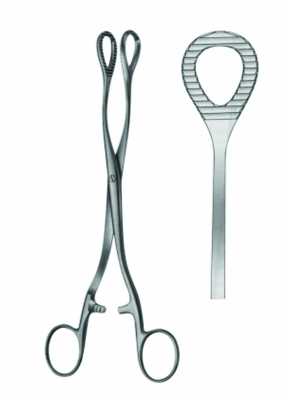

The Bladder Retractors AE 03 5728 are precision-engineered surgical instruments designed for optimal exposure and access during urological and general surgical procedures. These retractors are indispensable for gently elevating, retracting, and stabilizing the bladder and surrounding tissues during surgeries such as cystectomy, bladder tumor excision, urethral procedures, and other complex urological interventions. Their design emphasizes precision, safety, and ergonomic efficiency, enabling surgeons to maintain a clear operative field while minimizing trauma to delicate anatomical structures.

The blades of the Bladder Retractors are carefully contoured to provide secure, atraumatic retraction of bladder tissues. Smooth, precisely shaped surfaces allow controlled manipulation and optimal visualization of the operative site without causing injury to the bladder wall or adjacent structures. This careful design ensures maximum accessibility and visibility, enabling surgeons to operate efficiently and safely, even in confined or complex anatomical spaces.

Ergonomically designed handles provide comfort, superior control, and precision. Balanced weight distribution and smooth finger rings reduce hand fatigue, allowing surgeons to maintain steady and accurate movements during prolonged or intricate procedures. The lightweight yet sturdy construction ensures excellent maneuverability, enhancing procedural efficiency and patient safety.